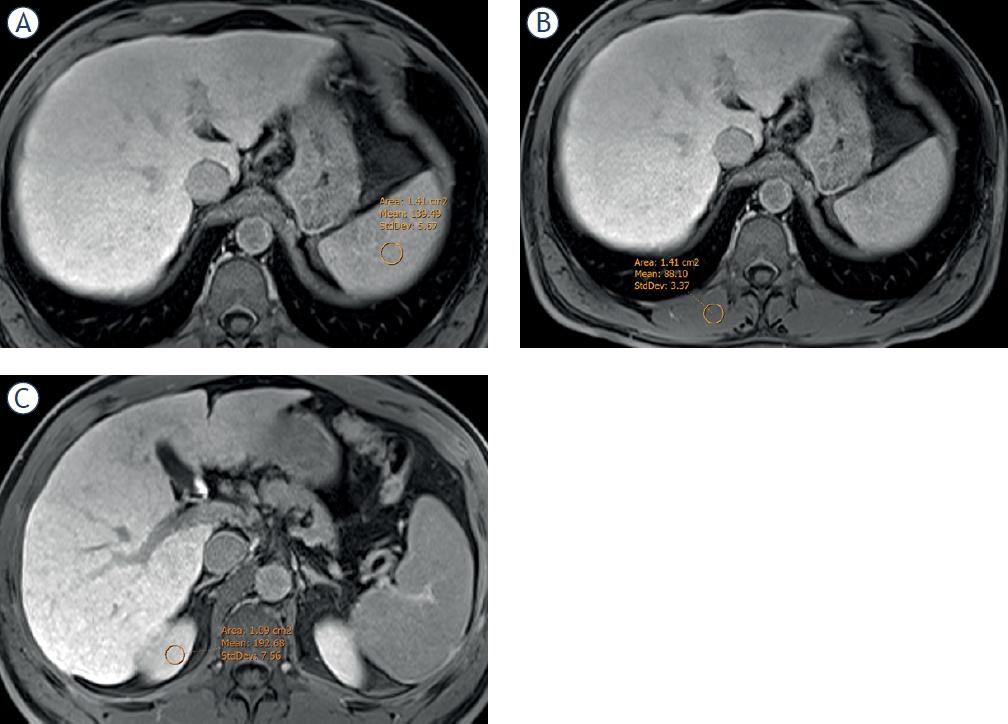

Liver to Spleen/muscle/Kidney Contrast Ratios: These indices determine the relationship between the SI of the liver and the SI of the spleen (LSCR), muscle (LMCR) and kidney (LKCR). To estimate the LSCR, an additional ROI was drawn on the spleen, over the same three images selected previously.26 (Figure 3A) For LMCR, an additional ROI with an average area of 100 mm2 was drawn on the right paraspinal muscle. (Figure 3B). Finally, for LKCR an additional ROI with an average area of 0,5 to 1 cm2 was drawn on the upper pole of the right kidney (Figure 3C).

Location of the region of interest in the 20 minutes hepatobiliary phase in the spleen (A), in the right paravertebral muscle (B), and in the upper pole of the right kidney (C) to calculate the different quantitative parameters of contrast liver uptake: spleen-liver intensity (SLI) and liver-spleen contrast ratio (LSCR), muscle-liver intensity (MLI) and the liver-muscle contrast ratio (LMCR) and kidney-liver intensity (KLI) and the liver-kidney contrast ratio (LKCR), respectively.